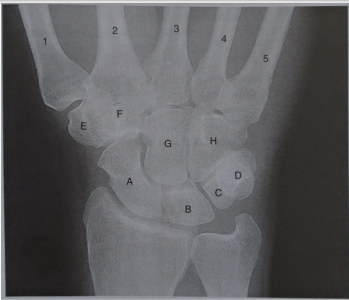

Associe as letras que estão no raios X em PA do punho com suas respectivas estruturas.

( 1 ) Capitato

( 2 ) Semilunar

( 3 ) Pisiforme

( 4 ) Hamato

( 5 ) Trapezoide

( 6 ) Escafoide

( 7 ) Trapézio

( 8 ) Piramidal

( ) A

( ) B

( ) C

( ) D

( ) E

( ) F

( ) G

( ) H

Marque a alternativa que tem a sequência CORRETA.